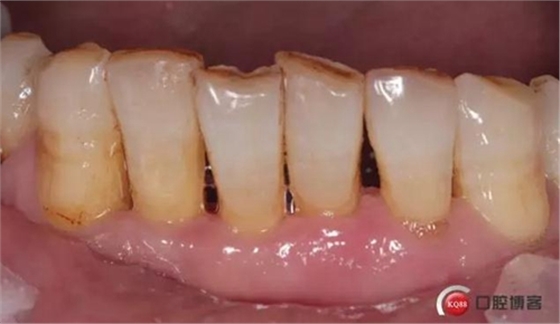

檢查:口腔衛(wèi)生狀況欠佳,牙面可見(jiàn)大量色素附著,牙石II°,尤以下頜前牙舌側(cè)及后牙頰側(cè)為重。牙齦紅腫,BI3-4°,PD下頜前牙區(qū)4-6mm。31松動(dòng)III°,溫度測(cè)試無(wú)反應(yīng),叩不適。32、41、42松II°+,32溫度測(cè)試遲鈍,叩(-)。

檢查:口腔衛(wèi)生狀況尚可,下頜前牙區(qū)牙齒鄰接可見(jiàn)食物殘?jiān)街?。牙齦色澤轉(zhuǎn)淡。

檢查:口腔衛(wèi)生狀況一般,下頜前牙區(qū)牙齦色澤尚可,牙齦位置退縮,松動(dòng)度減輕。